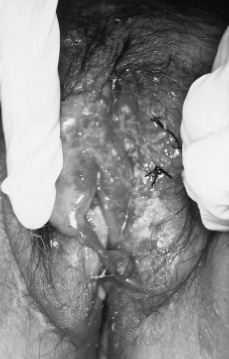

La biopsia vulvar fue informada como cuña cutánea con ulceración y abundante tejido de granulación por debajo de la misma, observándose una lesión granulomatosa formada por histiocitos, linfocitos y células gigantes tipo Langhans sin focos de necrosis epitelioides y sin relación con folículos pilosos. La tinción de PAS era negativa (Figs. 3 y 4).

Figura 3. Biopsia vulvar con ulceración y abundante tejido de granulación por debajo. Granuloma y células gigantes tipo Langhans x 250.

Figura 4. Granuloma y células gigantes tipo Langhans x 400.